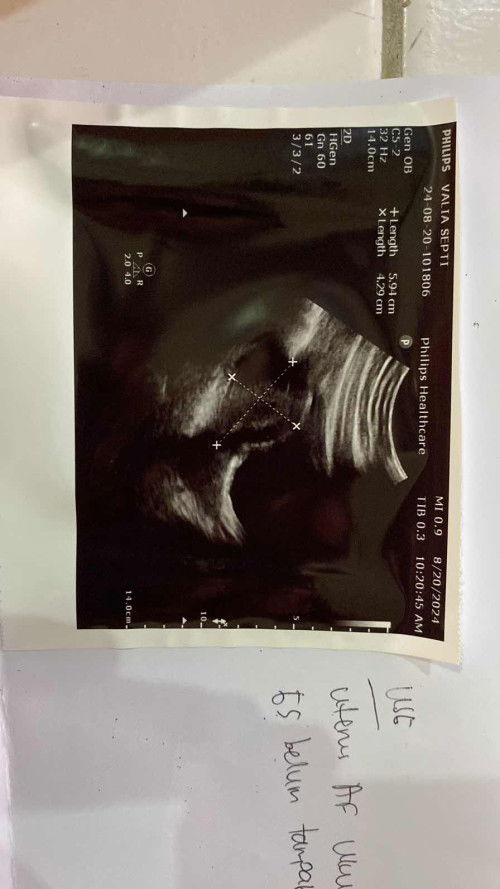

Tes positif, tapi belum ada janin

Hai bun, aku mau share.. tgl 17 agustus kemarin aku cek pake tespek hasilnya positif. HPHT ku tgl 10 juli kemarin. Trs aku cek ke dokter hasilnya begini. 2minggu lg dsruh kontrol lg ke dokter. Sampe skrg aku bngung, karna gaada ngerasa mual yg tiaphari gitu, pusing, atau tanda-tanda hamil lain. Belum juga haid. Ada yg sama spt ini kah?😔